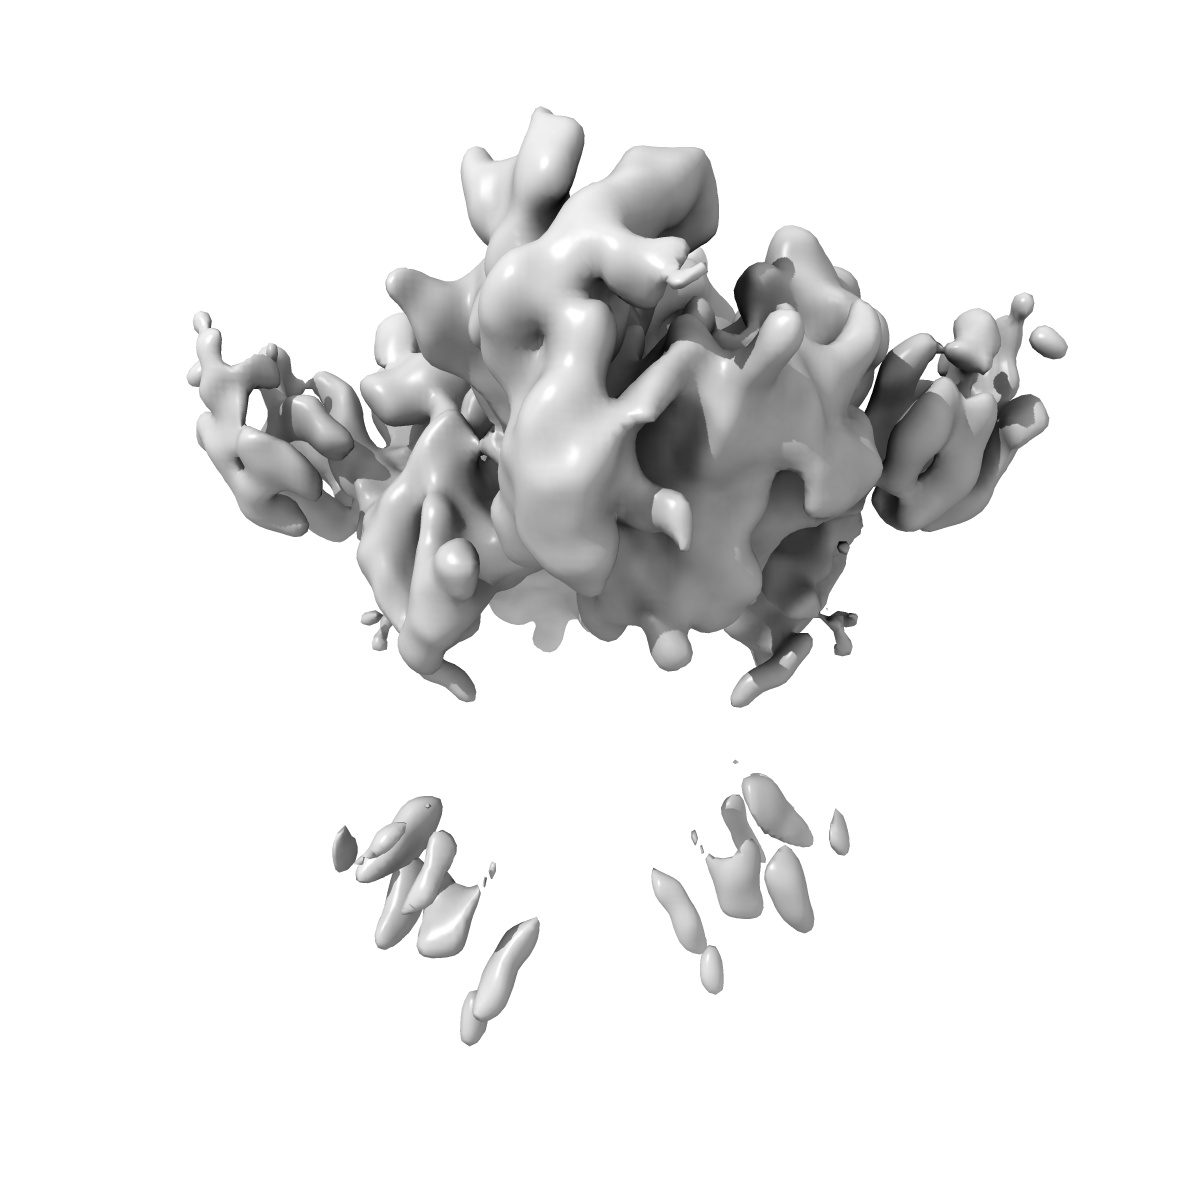

Insulin receptor ectodomain dimer complexed with two IRPA-9 partial agonists

Single-particle5.2 Å

Sample: IR-ECD dimer complexed with two IRPA-9 full agonists